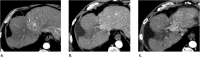

Computed tomography (CT) and magnetic resonance imaging (MRI) play critical roles for assessing treatment response of hepatocellular carcinoma (HCC) after locoregional therapy. Interpretation is challenging because posttreatment imaging findings depend on the type of treatment, magnitude of treatment response, time interval after treatment, and other factors. To help radiologists interpret and report treatment response in a clear, simple, and standardized manner, the Liver Imaging Reporting and Data System (LI-RADS) has developed a Treatment Response (LR-TR) algorithm. Introduced in 2017, the system provides criteria to categorize response of HCC to locoregional treatment (e.g., chemical ablation, energy-based ablation, transcatheter therapy, and radiation therapy). LR-TR categories include Nonevaluable, Nonviable, Equivocal, and Viable. LR-TR does not apply to patients on systemic therapies. This article reviews the LR-TR algorithm; discusses locoregional therapies for HCC, treatment concepts, and expected posttreatment findings; and illustrates LI-RADS treatment response assessment with CT and MRI.